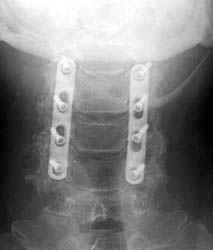

50-year-old male who presented with worsening gait, neck pain, upper

extremity pain, numbness, and occasional bowel and bladder incontinence. The

patient complained of increasing difficulty walking, neck stiffness, and leg

cramps, increasing upper extremity numbness, and dysthesia in hands and

forearms. The patient underwent C3-6 laminectomies with postero-lateral fusions.

AP and lateral radiographs taken 5 days after surgery demonstrate

typical laminectomy defects at C3-6. The posterolateral fusions appear intact

with bone grafting material faintly appreciated. The screws and plates are

intact and in appropriate positioning. |